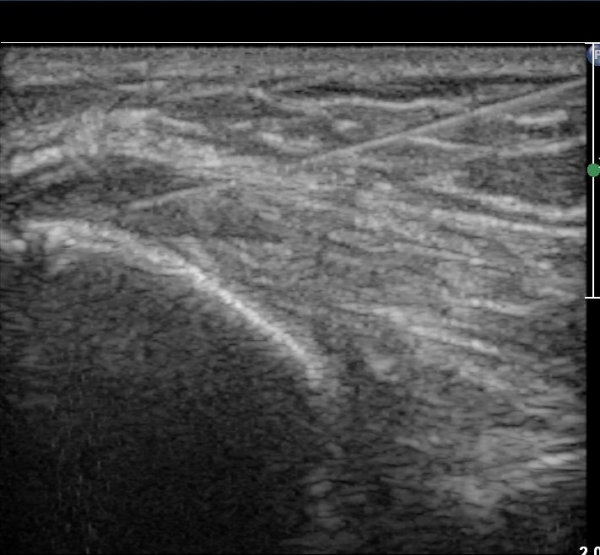

°í¿¡ÄÚ Å½ÃËÀÚ(ÇÏŰ½ºÆ½)·Î °üÂû ½Ã °Ç ºÎÂøºÎ°¡ °í¿¡ÄÚ ¼¶À¯ ¾ç»óÀ¸·Î Á¤»óÀûÀÎ ¼Ò°ßÀ» º¸ÀδÙ(±×¸² 4).

º´º¯ ºÎÀ§·Î ŽÃËÀÚ¸¦ À̵¿ÇÏ±â °Ç ºÎÂøºÎ Àú¿¡ÄÚ º¯¼ºÀÌ ¶Ñ·ÈÇÏ´Ù(±×¸² 5).

ÃÊÀ½ÆÄÀ¯µµÇÏ ÁÖ»çÄ¡·á »çÁøÀ¸·Î ¹Ù´ÃÀÌ º´º¯ ºÎÀ§¿¡ Á¤È®È÷ À§Çϰí ÀÖ´Â °ÍÀÌ º¸ÀδÙ(»çÁø 6).

Áֻ縦 ½ÃÇàÇÏ´Ï ÁÖ»ç¾×ÀÌ ¸¶Ä¡ ³¶Á¾¿¡ ÁÖ»çÇÏ´Â °Íó·³ ÁÖ»çµÇ¾î Àú¿¡ÄÚ º´º¯ ºÎÀ§°¡

ÆÄ¿­µÈ °ÍÀÓÀÌ È®ÀεȴÙ(÷ºÎ µ¿¿µ»ó).